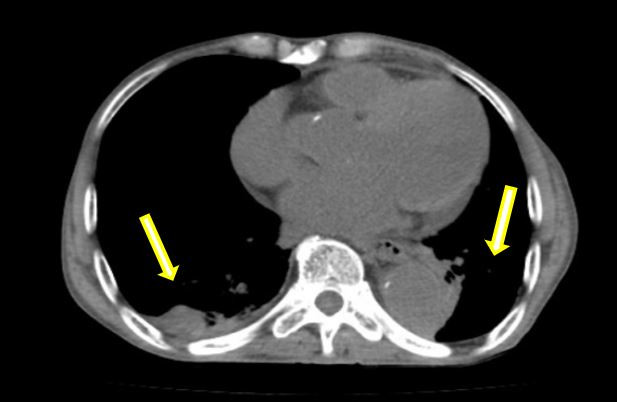

在患者轉(zhuǎn)運(yùn)過程中,血管外科急診團(tuán)隊(duì)、影像科、麻醉科、胸心外科、導(dǎo)管室、輸血科等相關(guān)科室已著手做好了急診相關(guān)預(yù)案。從患者的急診CTA上可以看到原有的胸主動(dòng)脈支架因血流動(dòng)力學(xué)影響,出現(xiàn)了近端Ⅰ型內(nèi)漏,大量血液經(jīng)由支架與主動(dòng)脈間的縫隙進(jìn)入假性動(dòng)脈瘤腔內(nèi),左側(cè)胸腔出現(xiàn)大量血腫,甚至出現(xiàn)了少量的心包積液。急診血常規(guī)顯示患者血紅蛋白才66g/L,顏老爺子已出現(xiàn)煩躁不安等譫妄表現(xiàn),為保障手術(shù)安全,團(tuán)隊(duì)立即聯(lián)系輸血科鄭春盛主任,有力地保障了患者術(shù)中用血。

術(shù)前:雙側(cè)胸腔大量積血,雙肺受壓(箭頭示)

術(shù)后:經(jīng)引流后胸腔大量積液消失,肺部壓迫解除(箭頭示)